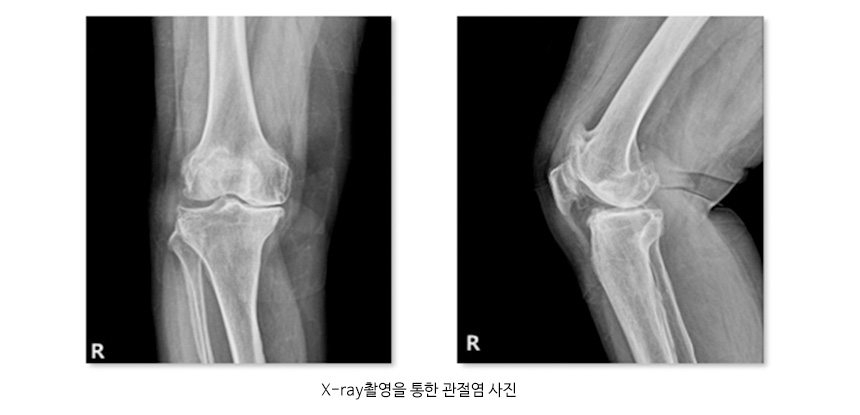

● 진단 퇴행성 관절염을 진단하기 위해서는 X-ray촬영을 통하여 관절염 여부를 판정하며, 동반된 연부조직의 이상이나 관절연골의 상태를 보기 위해 MRI 촬영을 하기도하며 혈액검사와 관절액을 검사하여 다른 원인에 의한 관절염의 여부를 확인하기도 합니다. ● 치료 퇴행성 관절염을 치료하기 위해서는 생활습관을 개선하고 약물요법으로 염증을 줄이고 재활치료를 시행하여 증상 완화와 근육위축 방지를 할 수 있으며, 비수술적 치료방법에도 불구하고 증상 호전이 없는 경우 관절경 및 인공관절 치환술을 시행하기도 합니다. 관절염 사진 및 인공슬관절 치환술 사진 ![]() ![]() |